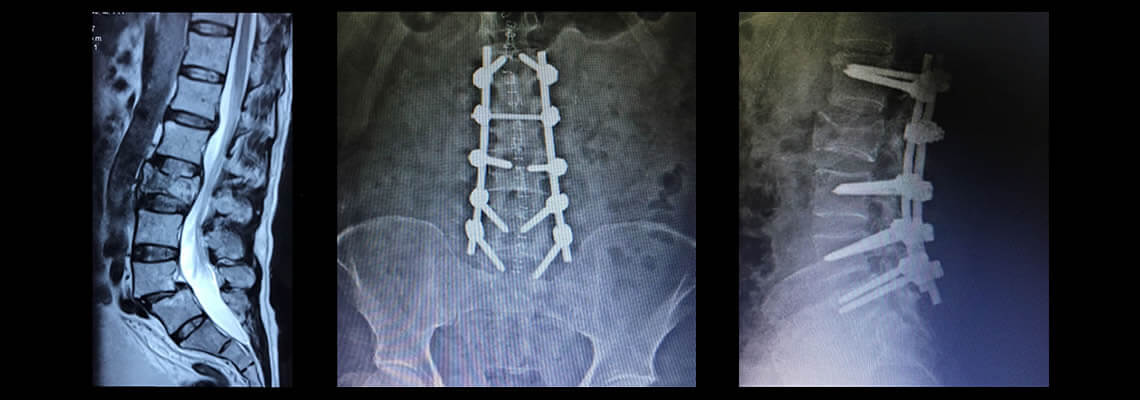

Hernia de Disto

¿Tienes una hernia de disco? ¿Dolor de Ciática? ¿Dolor de Espalda?